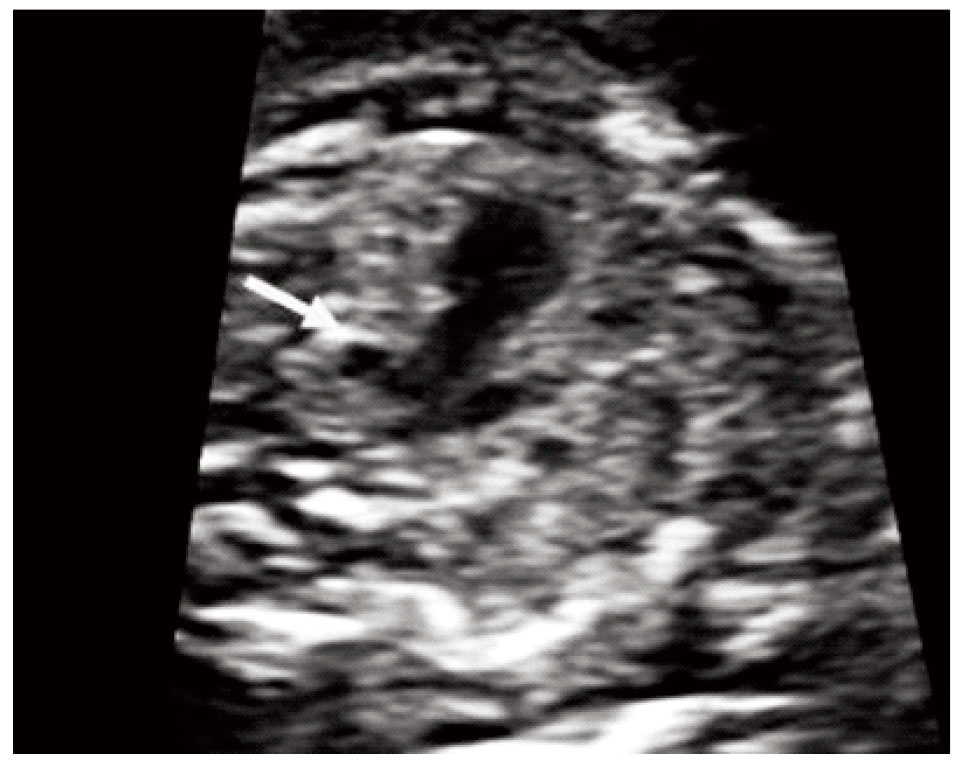

The stomach was present but located centrally rather than on the left side of the abdominal cavity (Figure 1). In addition the cardiac axis deviated to the left. Maternal biochemistry was normal (βhCG: 0.308 MoM, PAPPA: 0.518 MoM) and the risk for the common trisomies was low (1 in 11,941). Repeat ultrasound examination at 17 weeks showed that the stomach remained in central position, there was persistent left superior vena cava and the aorta had obviously smaller diameter than the pulmonary artery (Figures 2, 3). The results were confirmed by fetal echocardiography.Amniocentesis was performed at the request of the parents; the fetal karyotype was normal (46XY) and there were no additional findings from CGH arrays analysis. Fetal MRI at 24 weeks confirmed the central position of the stomach whereas no structural anomaly was detected. Repeat fetal echocardiography at 29 weeks showed normal growth of the aorta and the aortic arch, two morphologically left atria and interrupted inferior vena cava thus establishing the diagnosis of left atrial isomerism. Further investigations by Whole Exome Sequencing detected two missense variants of uncertain significance in the gene PKD1L1. Pathological mutations with heterozygosity in this gene have been associated with autosomal visceral heterotaxy. The parents were counseled by a clinical geneticist on the favorable prognosis in the absence of a heart defect and decided to continue the pregnancy. Repeat MRI scan at 35 weeks identified multiple small spleens and malrotation of the bowel.The infant was born by cesarean section at 38 weeks (birth weight 3,300 gr). The diagnosis was confirmed after birth. He is currently discharged at home and is scheduled for bowel surgery.

Figure 1. Cross‐sectional view of the fetal abdomen at 13 gestational weeks with central positioning of the stomach.